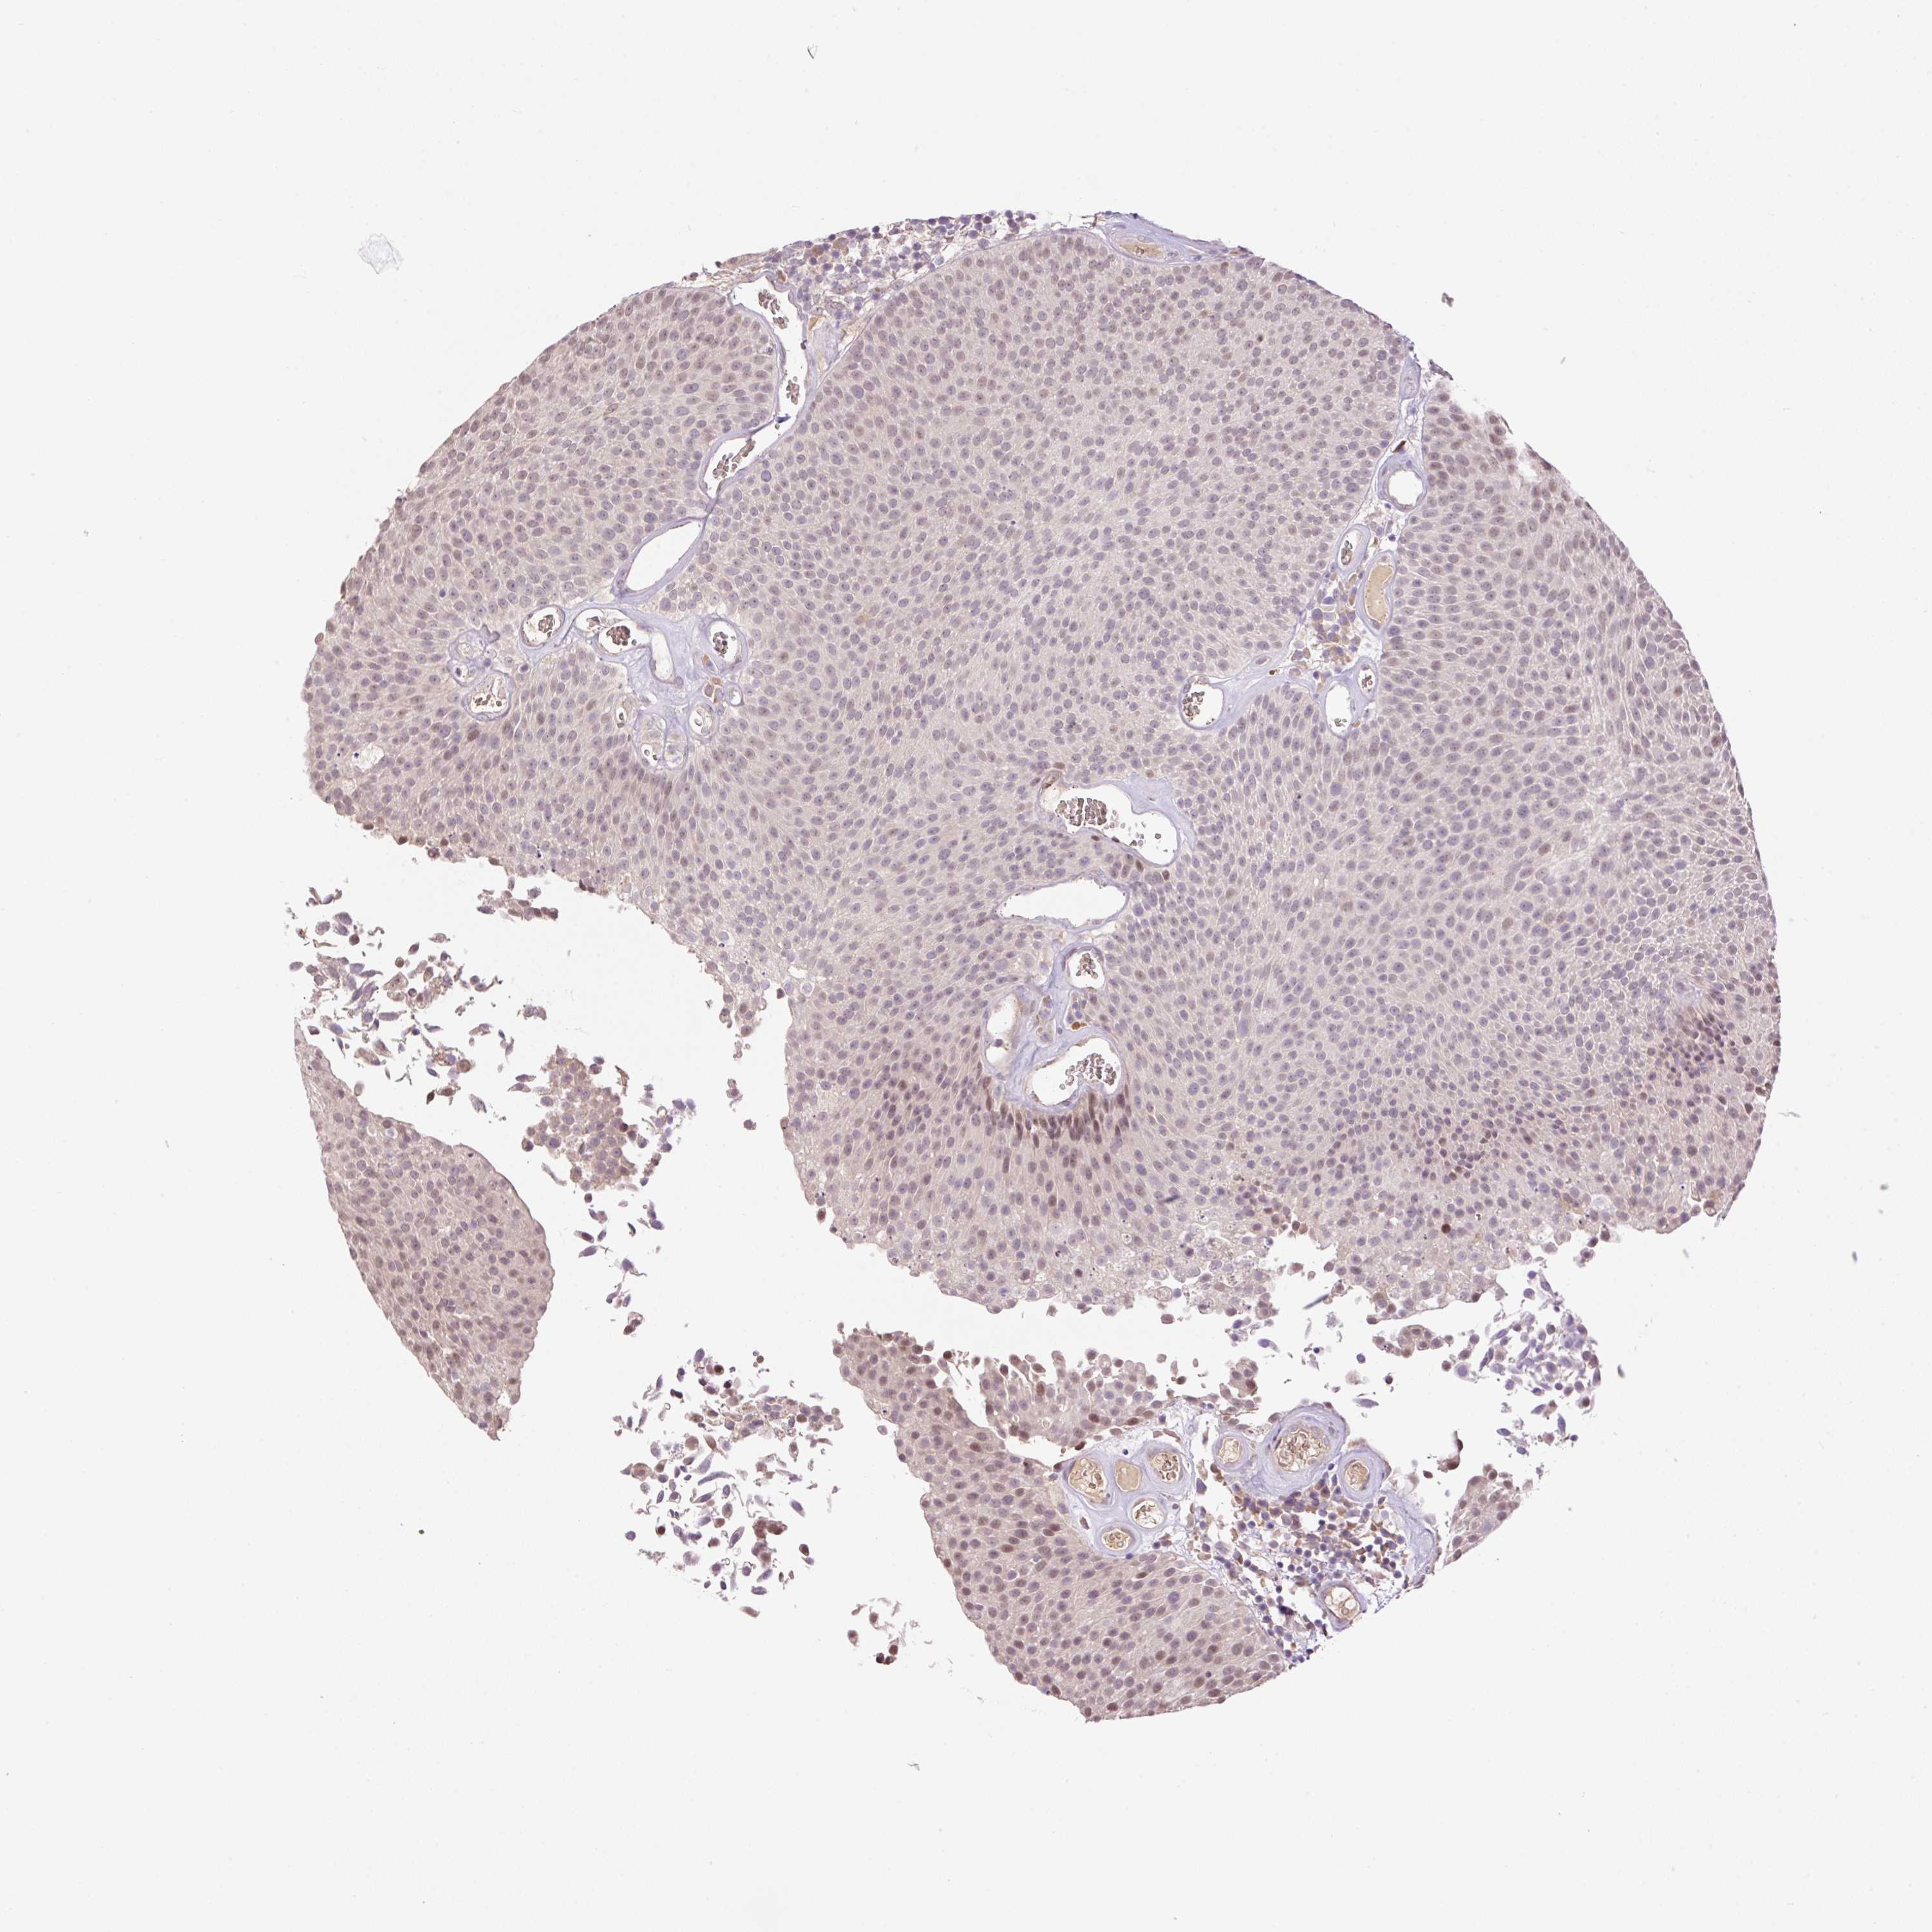

UROTHELIAL CANCER - Protein expressioni

A mouse-over function shows sample information and annotation data. Click on an image to view it in a full screen mode. Samples can be filtered based on level of antibody staining by selecting one or several of the following categories: high, medium, low and not detected. The assay and annotation is described here.

Note that samples used for immunohistochemistry by the Human Protein Atlas do not correspond to samples in the TCGA dataset.

Antibody stainingi

Antibody staining in the annotated cell types in the current human tissue is reported as not detected, low, medium, or high, based on conventional immunohistochemistry profiling in selected tissues. This score is based on the combination of the staining intensity and fraction of stained cells.

Each image is clickable and will lead to virtual microscopy that enables deeper exploration of all samples and also displays staining intensity scores, fraction scores and subcellular localization as well as patient and tissue information for each sample.

Antibody HPA055969

Antibody HPA062366

Staining

High

Medium

Low

Not detected

Intensity

Strong

Moderate

Weak

Negative

Quantity

>75%

75%-25%

<25%

None

Location

Nuclear

Cytoplasmic/membranous

Cytoplasmic/membranous,nuclear

Urothelial carcinoma, High grade

Urothelial carcinoma, NOS

Urothelial carcinoma, Low grade